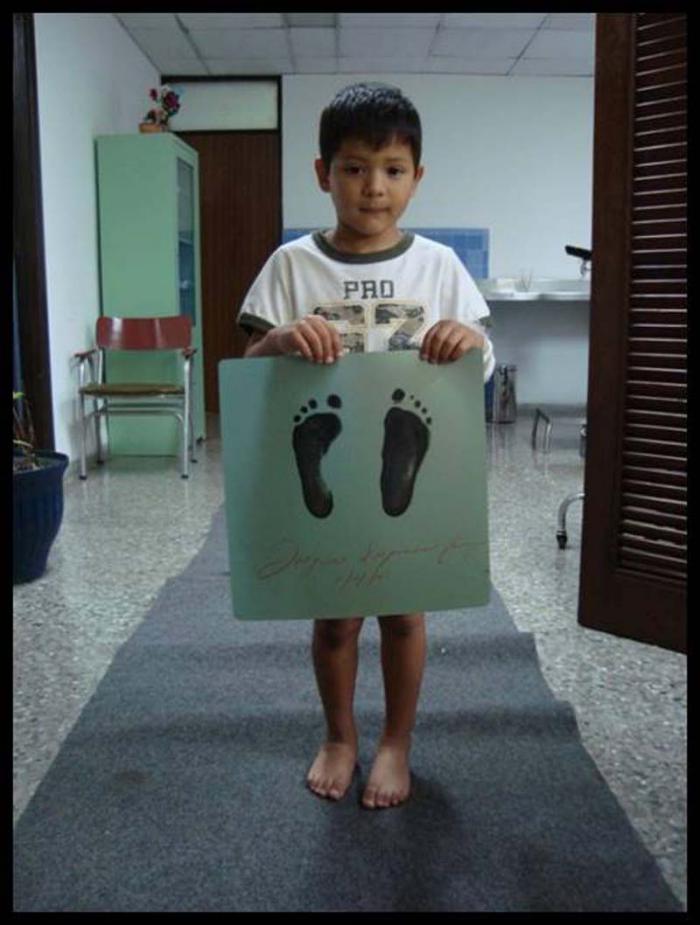

“¿Te gusta cómo quedaron?”. Se escucha una, dos, tres veces… y así hasta el último niño o niña, pasado el mediodía.

Ellos responden, desinhibidos… Él insiste. Conversan. Sonríen. Hay cierta complicidad que alcanzas a atrapar, y se repite... Definitivamente hay que tener don para los más pequeños. Aquí no falta.

¿Te gusta como quedaron?, se escucha.

Los niños no mienten, y sonríen. Tras el parabán, la licenciada en enfermería Sandra Arias Avilé cambia las vendas, retira suturas, aconseja…

Afuera, la complicidad tiene rostro y desenfado. ¡A ver, doctor, arrégleme estas planchas!